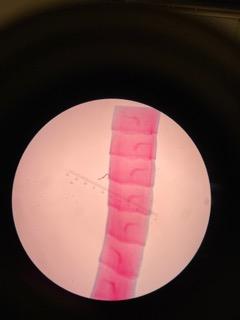

Dipylidium composite